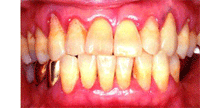

歯周病の説明・ブラッシング方法の説明

歯周病になっているかどうか?

図や写真で見せて、

具体的にご説明いたします。